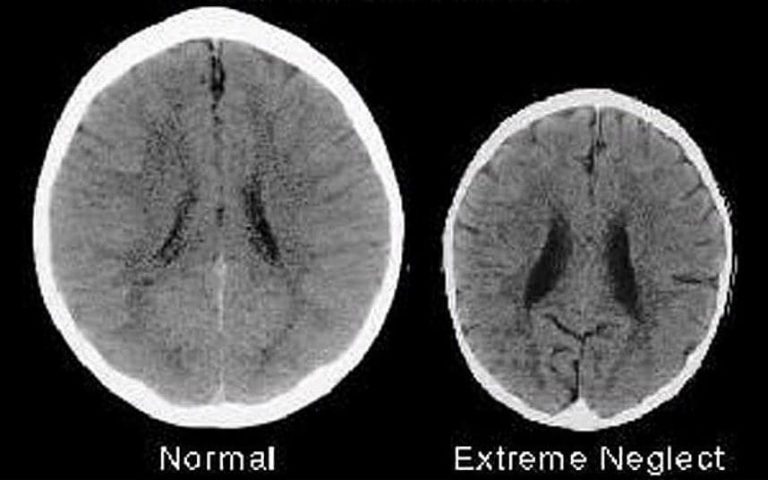

Imaginile cu raze X arata ca, creierul unui copil iubit, in varsta de 3 ani, este de doua ori mai mare decat creierul unui copil neglijat.

Aceasta imagine apartine celor 2 copii in varsta de 3 ani, primul a primit dragoste si afectiune, al doilea … nu.

Care este diferenta dintre creierul din stanga si cel din dreapta?

Dragostea.

Copilul al carui creier apare in stanga are parinti care il iubesc, il ingrijesc, ii vorbesc si interactioneaza pozitiv cu el.

Copilul al carui creier apare in partea dreapta a fost neglijat, ignorat si abuzat.

“Copilul din dreapta se va dezvolta intr-un adult mai putin inteligent, mai putin capabil sa empatizeze cu altii, mai probabil sa devina dependent de droguri si implicat in crime violente … sa dezvolte probleme de sanatate mentala dar si alte probleme serioase”, spune un articol publicat in The Telegraph in 2012.